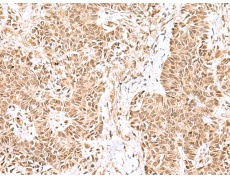

IHC positive control: |

Human esophagus cancer and Human ovarian cancer |

IHC Recommend dilution: |

25-100 |